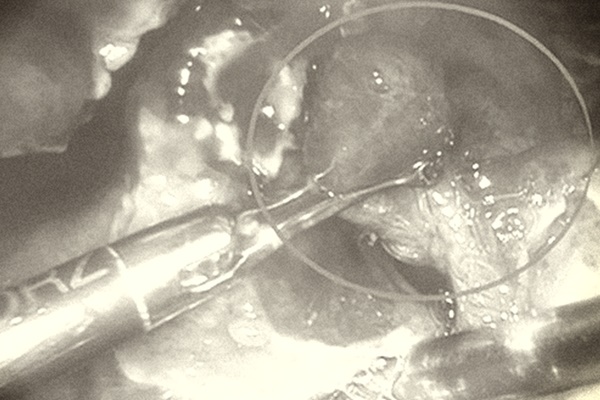

Vụ nghi viêm ruột thừa, cắt vòi trứng ở Bình Dương: Bác sĩ nói gì?-1

Người thân chị T. yêu cầu bác sĩ giải thích việc cắt buồng trứng của bệnh nhân. Ảnh cắt từ clip.